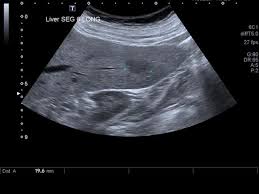

Colorectal cancers often spread before the initial tumor is detected, according to a new stanford study. This process by which cancer cells spread to other body parts is called metastasis. Cancer that starts in your colon can sometimes spread to other parts of your body, including the liver. Most cancer researchers have assumed that the spread, or metastasis, of tumors typically occurs later in the disease process. Biologic agents have assumed a major role in the treatment of metastatic cases. The process by which cancer cells spread to other parts of the body is called metastasis. Stage 4 colon cancer is the most advanced stage of the disease and may also be referred to as metastatic colon cancer. This means it has spread to regional or distant sites, such as other organs or lymph nodes. Colorectal cancer (crc) is the third most common cancer worldwide 1.approximately 56% of patients with crc die from their cancer 2.development of metastasis is a concern for patients and. With stage 3 colon cancer, there will be a positive finding of a primary tumor and regionally affected lymph nodes but no signs of metastasis. The most common site of metastases for colon or rectal cancer is the liver. Cancers that affect either of these organs may be called colorectal cancer. If the cancer spreads to other parts of the body, it is called metastatic colorectal cancer (mcrc), or stage 4 colorectal cancer.

The most common site of metastases for colon or rectal cancer is the liver. This is also referred to as advanced colon cancer or stage iv colon cancer. Most cancer researchers have assumed that the spread, or metastasis, of tumors typically occurs later in the disease process. Before saying anything else we need to point out that not all stage 4 colon cancers are alike. This means that the cancer cells have spread beyond the colon to surrounding organs or distant parts of the body.